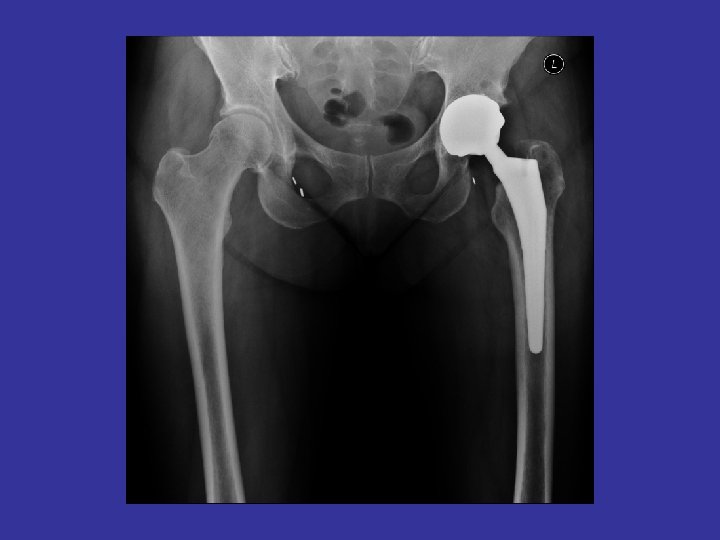

Joints – 2 bones come together. Held together by ligaments. Cushioned by cartilage. Lubricated by synovial fluid • Types of joints: – Ball-and-socket shoulder & hip